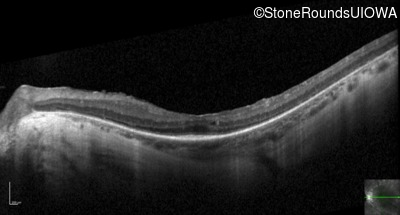

Optical Coherence Tomography - Right - 20/50 +1

Exemplar / OCT Stack